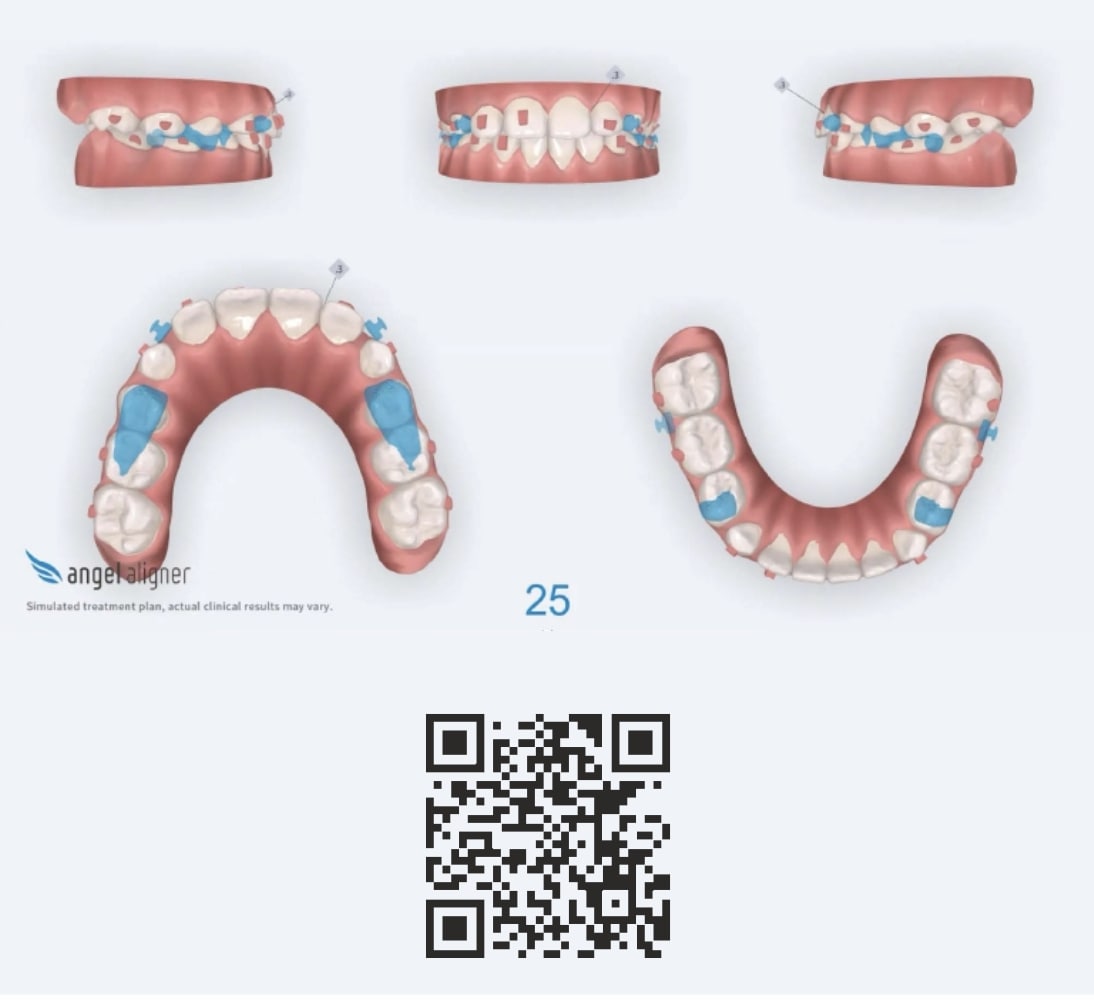

Number of aligners: 25

Malocclusion A6 Correction of Mandibular Retrusion in Growth phase patient | Skeletal Class II | Class II Division 1 malocclusion | Deep bite | Mixed dentition

Protocoles and features A6 Mandibular advancement

- Upper Archform enlargement (dental expansion)

- Normalize Overjet/Overbite (Lower Posterior Extrusion)

- Alignment/Leveling Both Arches

- Mandibular Advancement (A6 protocol) + angelBuon for Class 2 Elastics (Night Time)

Treatment setup

Treatment progress